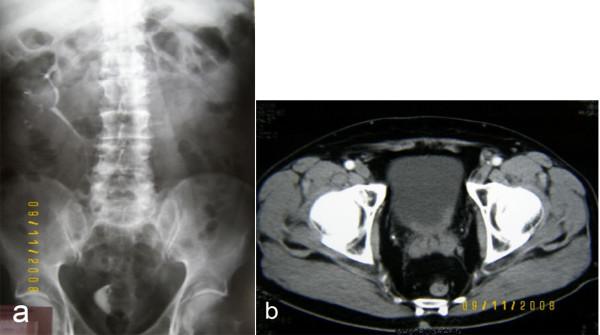

A 69-year old male patient was diagnosed with a primary mucinous adenocarcinoma of the bladder after undergoing a transurethral resection of a bladder tumour and complete examination of the entire gastrointestinal tract to rule out other primary cites. Immunohistochemistry confirmed the nature of the tumour. The patient underwent a radical cystoprostatectomy with en block bilateral pelvic lymphadenectomy and urinary diversion with a Bricker ileostomy.

病例介绍